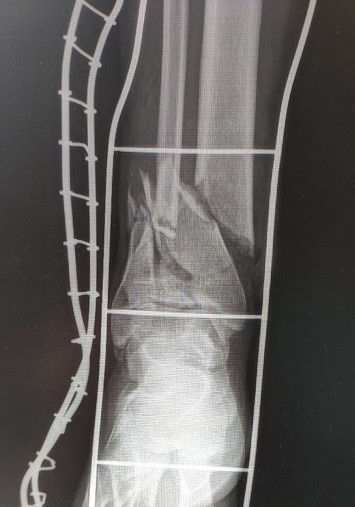

Jučer, lipa grupica dobro raspoloženih lokalnih aseva koristi par uri suhog vrimena za bouldering na idiličnoj Turskoj kuli. Nažalost, u klasiku Kvasimodo, našem prijatelju Igoru Grmuši puca hvatište na samom izlazu iz smjera, nezgodno pada i doživljava otvoreni prijelom potkoljenice. Jučer je bila jedna operacija, danas druga - da je ko drugi zabrinuli bi se - al Grmi je zmaj, bit će to dobro!